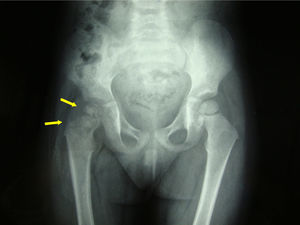

Paciente de 2 años de edad, de origen rumano, sin antecedentes de interés, que consultó por cojera de miembro inferior derecho de 3 meses de evolución. La niña estaba afebril y en la inspección se observó rechazo a la deambulación y al apoyo de dicha extremidad. En la exploración se apreció limitación y dolor a la rotación externa y abducción de la cadera. En la radiografía simple se observó desestructuración de la cabeza femoral (fig. 1). Ante la sospecha de osteomielitis se solicitó una resonancia magnética que mostró hallazgos compatibles con artritis séptica coxofemoral con osteomielitis proximal del fémur (fig. 2a y b).

Doce meses después de completar el tratamiento la paciente está asintomática, la marcha y la exploración de la cadera no presentan alteraciones, pero en la radiografía persiste una alteración de densidad a nivel de cabeza femoral, sin colapso de ésta.